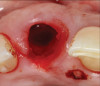

8. Tooth No. 8 with diagnosis of Grade III socket, requiring extraction followed by guided bone regeneration and a rotated pedicle flap to gain hard and soft tissue for future implant placement.

Figure 8

9. Tooth No. 8 with diagnosis of Grade III socket, requiring extraction followed by guided bone regeneration and a rotated pedicle flap to gain hard and soft tissue for future implant placement.

Figure 9

10. Tooth No. 8 with diagnosis of Grade III socket, requiring extraction followed by guided bone regeneration and a rotated pedicle flap to gain hard and soft tissue for future implant placement.

A 56-year-old female patient was referred for the evaluation of tooth No. 8 (Figure 4 and Figure 5). A periapical radiograph indicated that the tooth had undergone apicoectomy and received an excessively long post (Figure 6), and a cone-beam computed tomography (CBCT) scan of the site revealed a lack of buccal plate bone (Figure 7).

Based on the single extraction socket roadmap developed by El Chaar and colleagues, the socket of tooth No. 8 was diagnosed as Grade III and would require initial treatment that included the extraction of failing tooth No. 8 followed by simultaneous guided bone regeneration and soft-tissue augmentation by means of a rotated palatal pedicle flap (Figure 8 through Figure 11).27,28 The principles of and guidelines for both the ridge augmentation and rotated pedicle flap have been described in the literature and will not be focused on in this case report.27-30 The patient was temporized with a bonded Maryland bridge that was adjusted to avoid creating pressure on the tissue during healing (Figure 12).